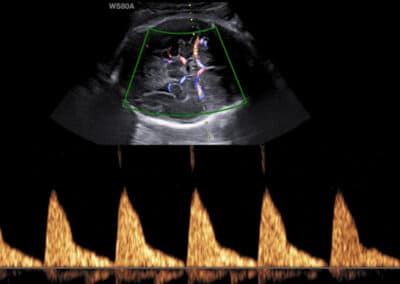

Dopplerovské vyšetření průtoku v arteria cerebri media

Co je to Dopplerovské vyšetření? Dopplerovské vyšetření je speciální typ ultrazvukového vyšetření, který se používá především k zobrazení průtoku krve, a to buď prostřednictvím barvy (tzv. barevné mapování) nebo křivky (tzv. pulzní vlna). Komu se doporučuje provedení Dopplerovského vyšetření krevního oběhu plodu a placenty? Toto vyšetření je velmi důležité u všech těhotenství, kde je zjištěno větší zpomalení růstu miminka. Pokud je totiž hmotnost miminka menší, než je v daném stáří miminka očekáváno, jen Dopplerovské vyšetření pomůže rozlišit, zda se jedná pouze o konstitučně menší miminko (obvykle v souvislosti s menší velikostí rodičů a miminek v rodině), nebo zda dochází ke snižování funkce placenty a miminko je menší, protože nedostává dostatek živin a kyslíku. Jaké cévy se při Dopplerovském vyšetření krevního oběhu placenty a plodu vyšetřují? Funkce placenty se hodnotí vyšetřením průtoku krve v pravé a levé děložní tepně (arteria uterina). Stav krevního oběhu miminka se hodnotí vyšetřením průtoku krve v pupečníkové tepně (artria umbilicalis), střední mozkové tepně (arteria cerebri media) a v ductus venosus (céva přítomna pouze před narozením). Může Dopplerovské vyšetření provádět každý gynekolog? Dopplerovské vyšetření je složitější a nelze provádět na všech ultrazvukových přístrojích. Komplexní hodnocení všech potřebných cév proto zpravidla provádějí pouze lékaři ve specializovaných centrech. I na toto vyšetření existuje certifikát od Fetal Medicine Foundation v Londýně. Seznam všech českých FMF certifikovaných lékařů najdete ZDE .